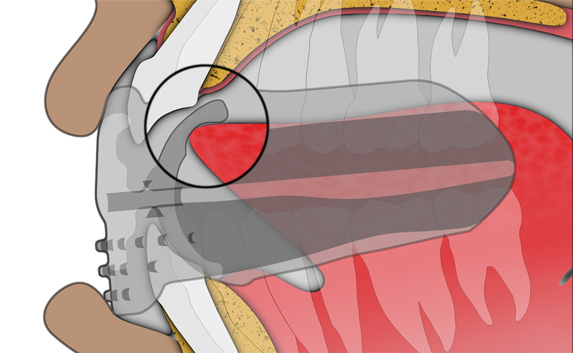

The B1 focuses on establishing nasal breathing and myofunctional habit correction for patients who are using braces. It is soft and flexible, giving the best compliance, while being adaptive to any arch form and malocclusion. It has small breathing holes to establish continuous nasal breathing and myofunctional features to promote correct habits. It also features braces channels to accommodate brackets and wires. The B1 is ideal for initial levelling and alignment with fixed orthodontics but can also be used throughout the entire orthodontic treatment plan.